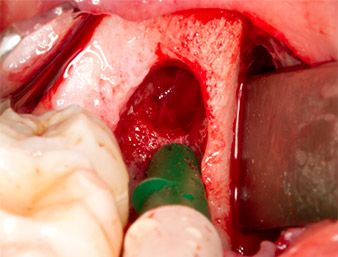

Periapical inflamed tissue was also removed very carefully with a manual excavator. Fig. 12 shows the empty alveole with exposed inferior alveolar nerve.

Subsequently, the autogenous bone tissue (Fig. 13) was placed into the alveole and the surrounding bone defect (Fig. 14). Collagen fleece covered the bone chips up to bone level as protection for the exposed nerve (Fig. 15). Sutures using vicryl thread, USP 4.0, were used to close the opened up soft tissue (Fig. 16). An Ibuprofen preparation (Seractil 400 mg, 3x1) and an antibiotic consisting of amoxicillin and clavulanic acid (Augmentin 1 g, 2x1) were prescribed postoperatively.